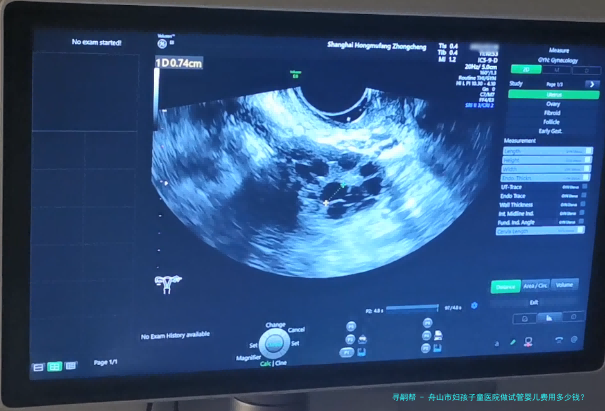

希望拥有本人的宝宝,但因为诸多原因无从自然受孕,试管婴儿就成为无数家庭的曙光。舟山市作为一个享有许多优质医疗机构之处,也提供着完备的试管婴儿服务。哪样舟山市妇孩子童医院做试管婴儿费用多少钱?成功率怎样呢?

舟山市妇孩子童医院是一家集医疗、教学、科研为一体的综合性三级妇产专科医院。医院成立于1958年,拥有先进的医疗配备和专业的医护集体,专心于为女性及儿童提供优质的医护服务。医院一向坚持“以人为核心”的观念,承继“精良、规范、高成效”的服务宗旨,为患者提供全面性、个体化的服务。